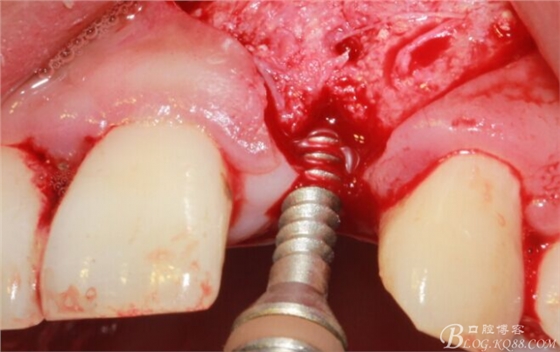

徹底搔刮拔牙窩,偏腭側(cè)備洞

順利植入植體,扭力30N。三壁骨,感覺美美的。